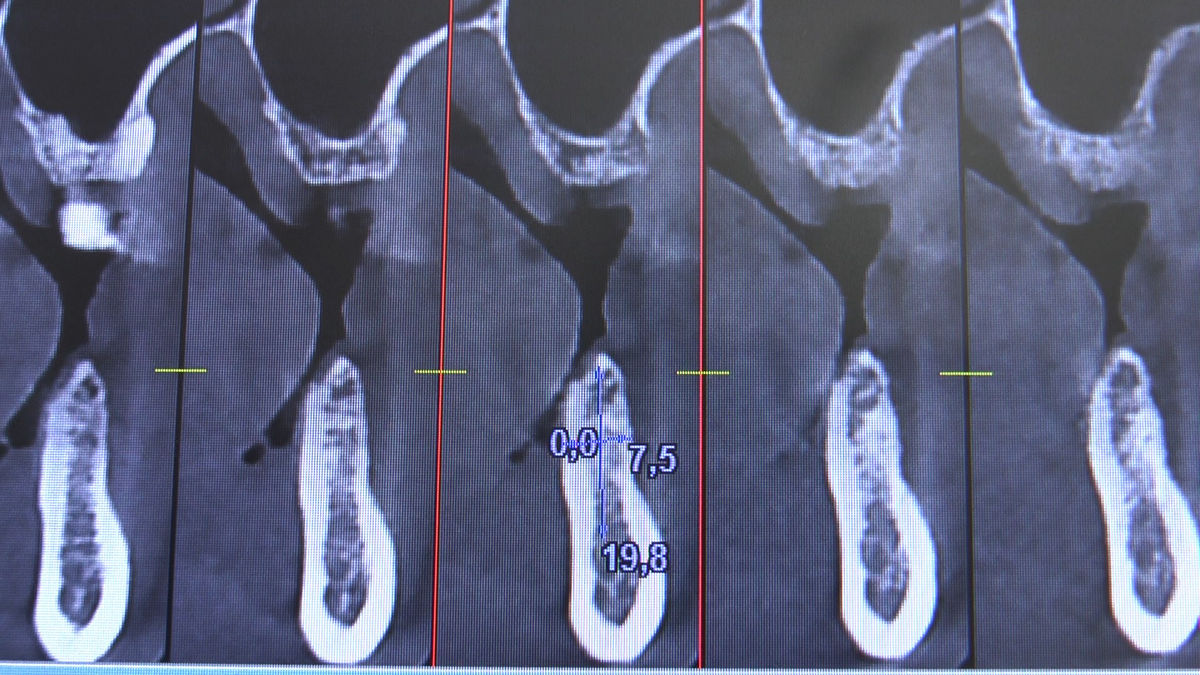

Tuż przed 100 Rocznicą Odzyskania Niepodległości, 9 i 10 listopada 2018 roku, kursanci VI Sezonu Practiculum Implantologii odbyli 7 Sesję. Dwa dni intensywnego szkolenia poświęcone zostały na zabiegi z zakresu chirurgii implantologicznej. Kursanci wykonali szereg zabiegów u Pacjentów pod kierunkiem Mentorów – dr n.med. Violetty Szycik i dr n.med. Magdaleny Kisłowskiej-Syryczyńskiej. Jak zwykle nie zaliczały się one do najłatwiejszych. W większości były przeprowadzone w arcytrudnych warunkach wynikających przede wszystkim ze stanu tkanki kostnej oraz stanu zdrowia, co wymagało precyzyjnego planowania. Z zabiegów skorzystało 17 Pacjentów, także z zastosowaniem znieczulenia ogólnego w formie sedacji dożylnej. Wszczepiono 23 implanty, wykonano zabiegi natychmiastowej implantacji po mnogich ekstrakcjach, przeprowadzono zabiegi augmentacji oraz 3 zabiegi sinus lift z zastosowaniem preparatów kościozastępczych i PRF. Wszystkie zabiegi przeprowadzane zostały zgodnie z planem i dużym stopniem samodzielności, który odpowiada zakresowi poszerzających się umiejętności szkolących się lekarzy. W panelu edukacyjnym Sukces Twojego Biznesu odbyły się pierwsze zajęcia z NLP. Kolejna 8 sesja już na początku grudnia.